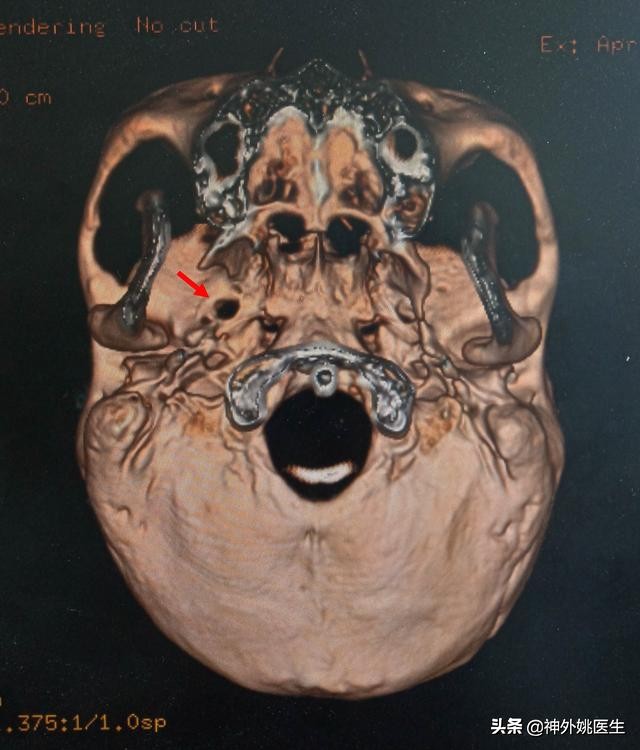

头CT检查:(图1、2)

图1 后颅窝未见占位性改变。

图2 卵圆孔形态规则,宽大(红色箭头所示)。